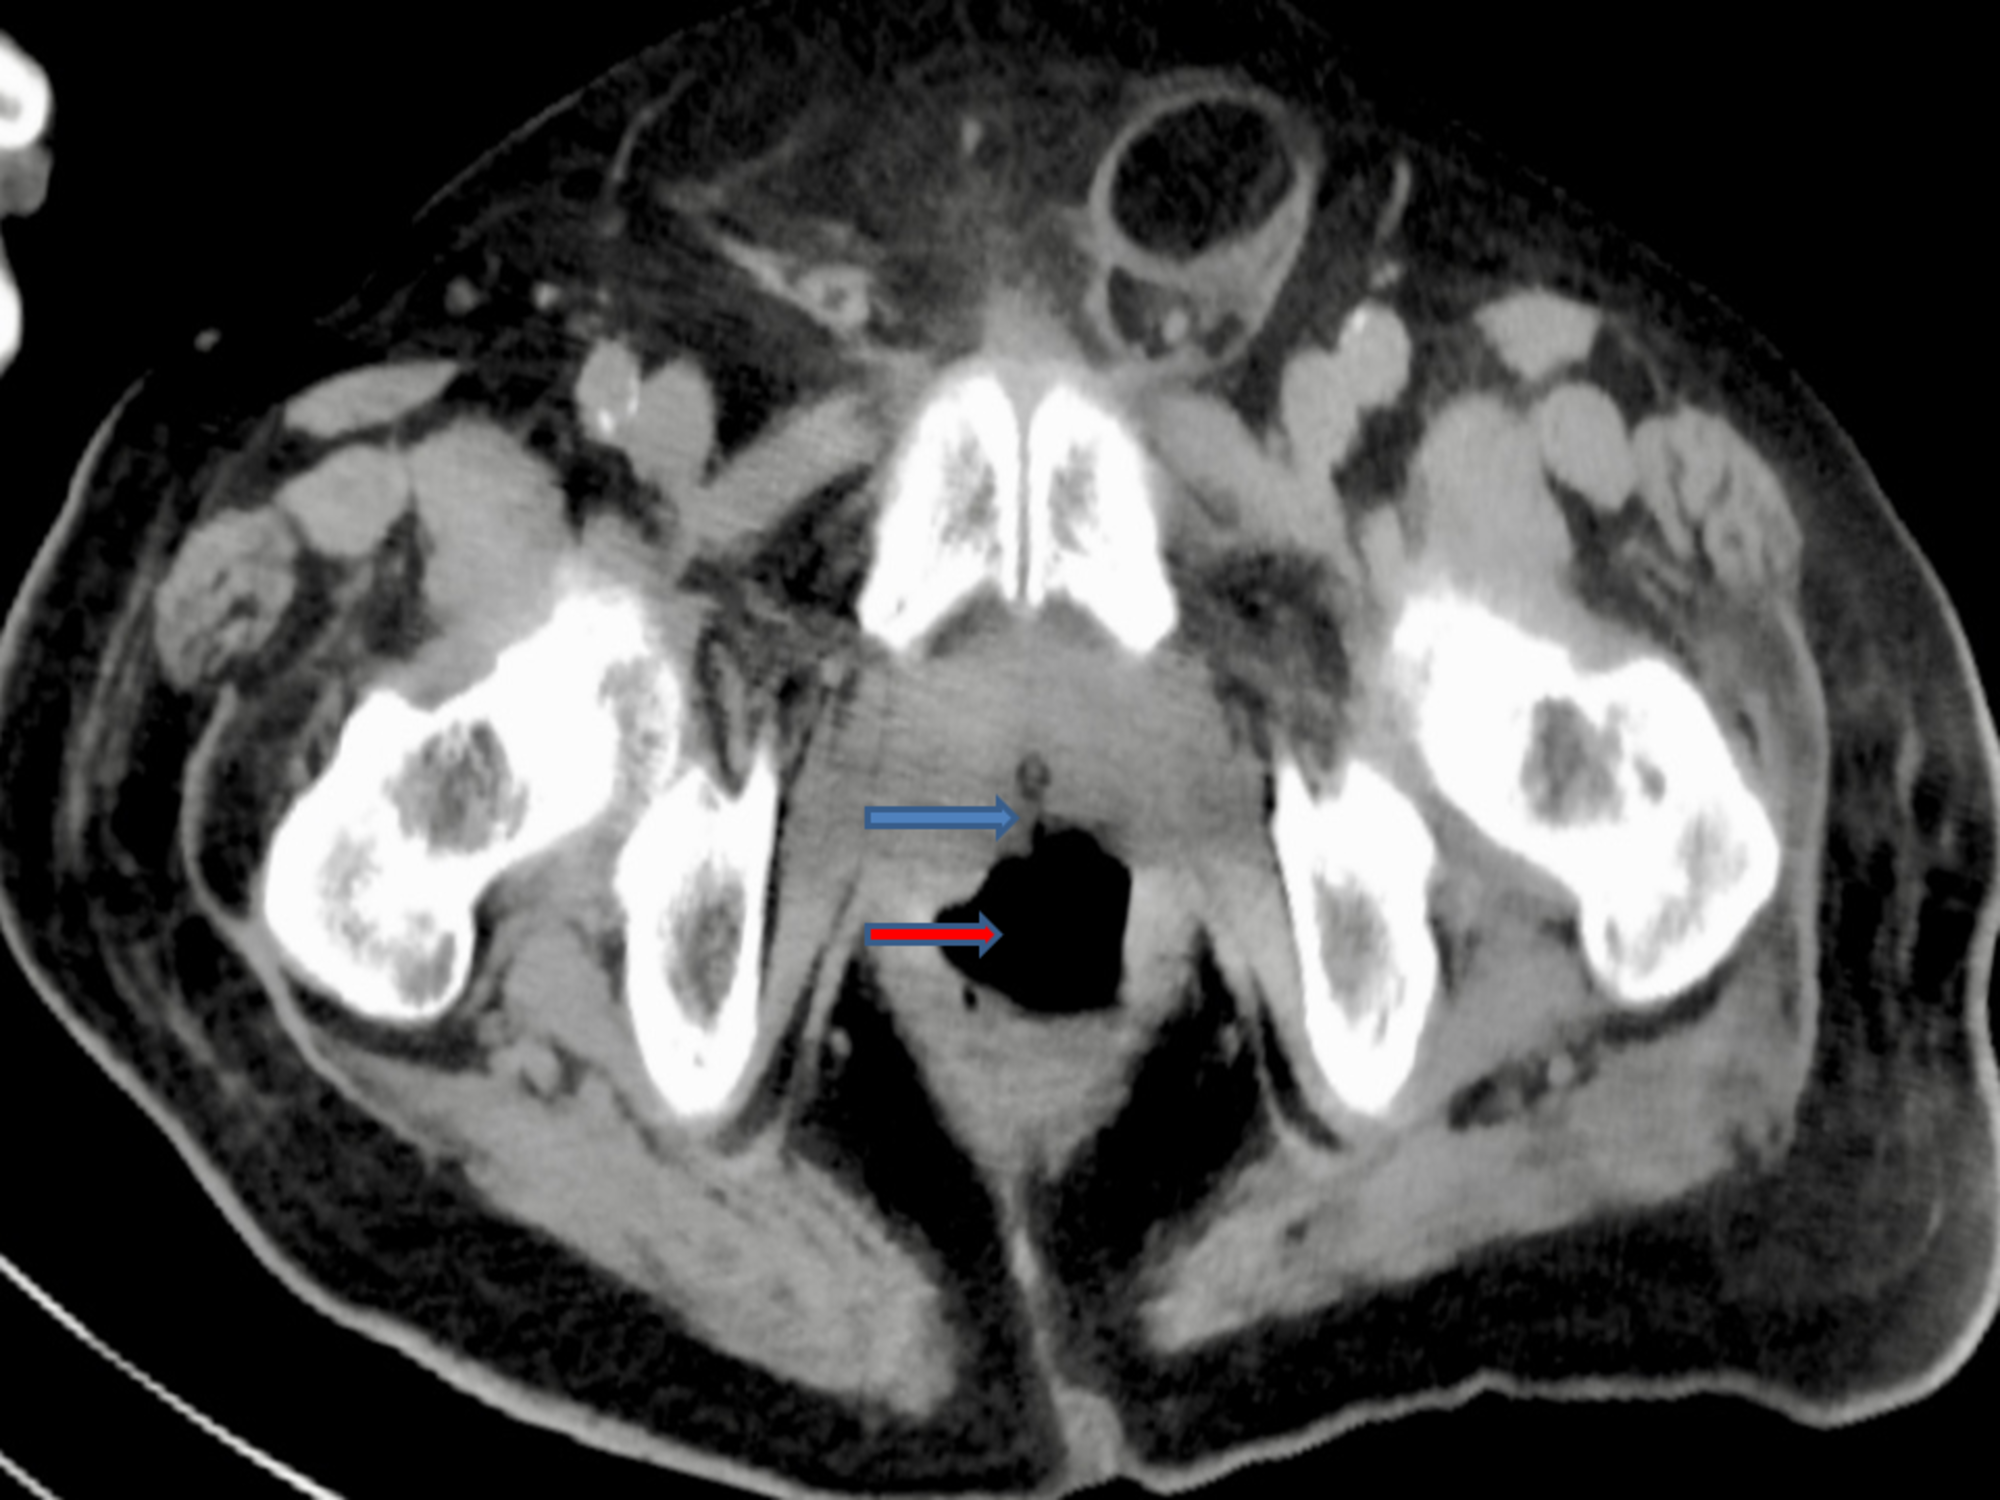

An 82-year-old male with a history of type 2 diabetes mellitus, hypertension, benign prostatic hyperplasia (BPH) with a size of 40 gram presented with asthenia, suprapubic pain, and distension of the lower abdomen. He underwent transurethral resection of prostate (TURP) for his BPH one week prior to admission and had an indwelling Foley’s catheter (due to urinary incontinence) at presentation. He also complained of non-bloody, watery diarrhea with four to five episodes per day for five days. He denied fever, cloudy urine, purulent urethral secretion, or any back pain. He also denied any prior history of radiotherapy or other gastrointestinal (GI) surgery related to the colon. At presentation, the patient was alert, awake, and cooperative and his vital signs included a temperature of 98.6° F, respiratory rate of 14 per minute, pulse of 86 beats per minute, BP of 113/56 mm Hg, and saturating 99% in room air. The physical examination revealed an indwelling Foley catheter with an attached right thigh bag showing clear urine. Laboratory investigations were notable for a slight elevation of the creatinine from the baseline. The urinalysis was positive for leukocyte esterase and nitrates, five to 15 red blood cell/high power field (HPF), and 30-50 white blood cell/HPF. The stool culture revealed no growth of microorganisms. The patient was started on intravenous (IV) normal saline and IV ceftriaxone 1 gram daily for a suspected urinary tract infection. Computed tomography (CT) of the abdomen and pelvis with IV contrast demonstrated findings consistent with a RUF. Cystourethrogram under fluoroscopy showed the extravasation of contrast into the rectum, which is also consistent with a rectourethral fistula (RUF) (Figure 1).

The abdominal and pelvic CT scan also showed RUF (Figures 4-5).